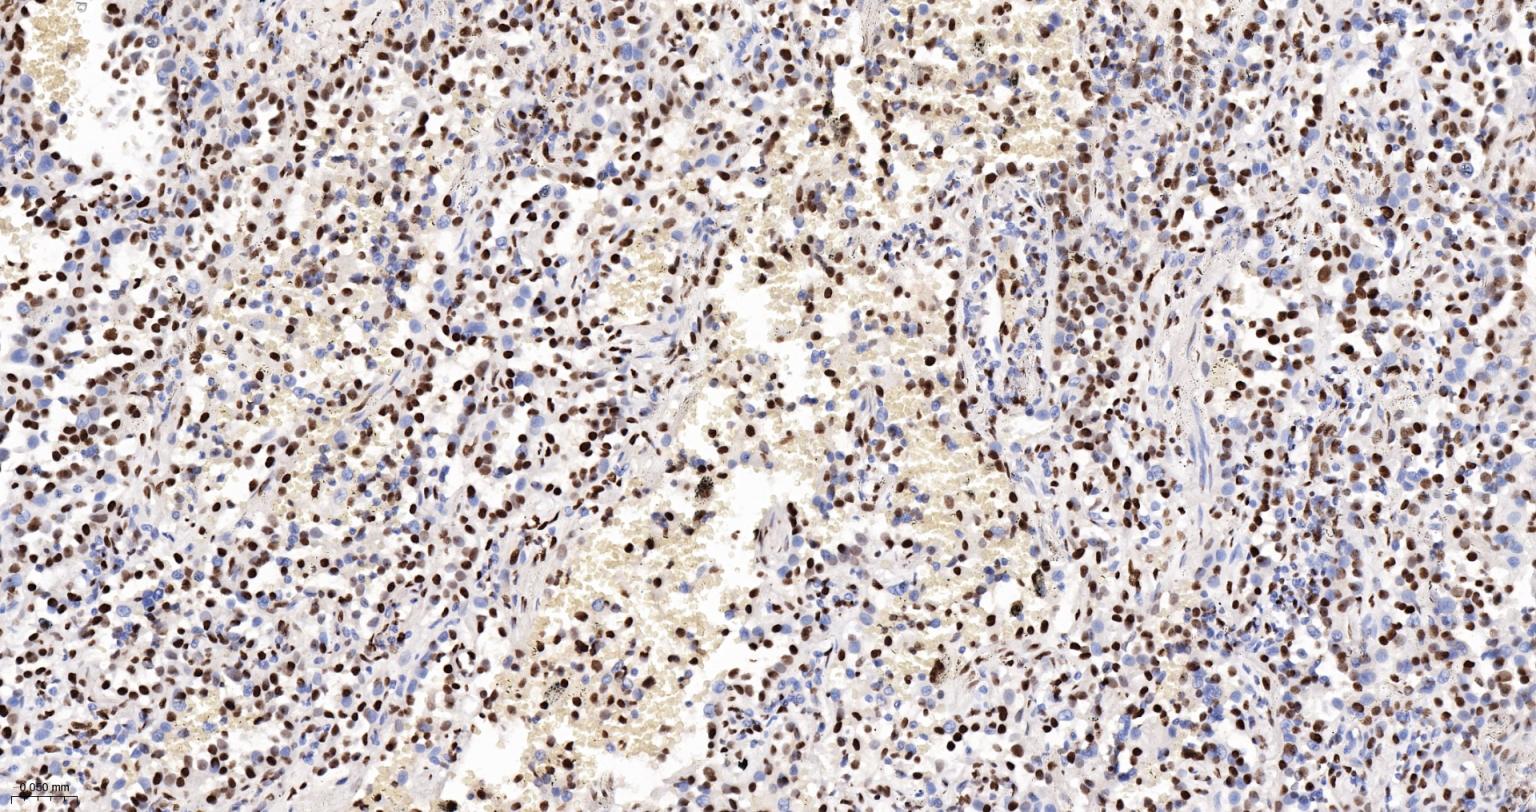

Paraformaldehyde-fixed, paraffin embedded Human Pancreatic Cancer; Antigen retrieval by boiling in sodium citrate buffer (pH6.0) for 15 min; The section was incubated with SFPQ Monoclonal Antibody, Unconjugated (bsm-61746R) at 1:200 overnight at 4°C, followed by conjugation to the bs-0295G-HRP and DAB (C-0010) staining.